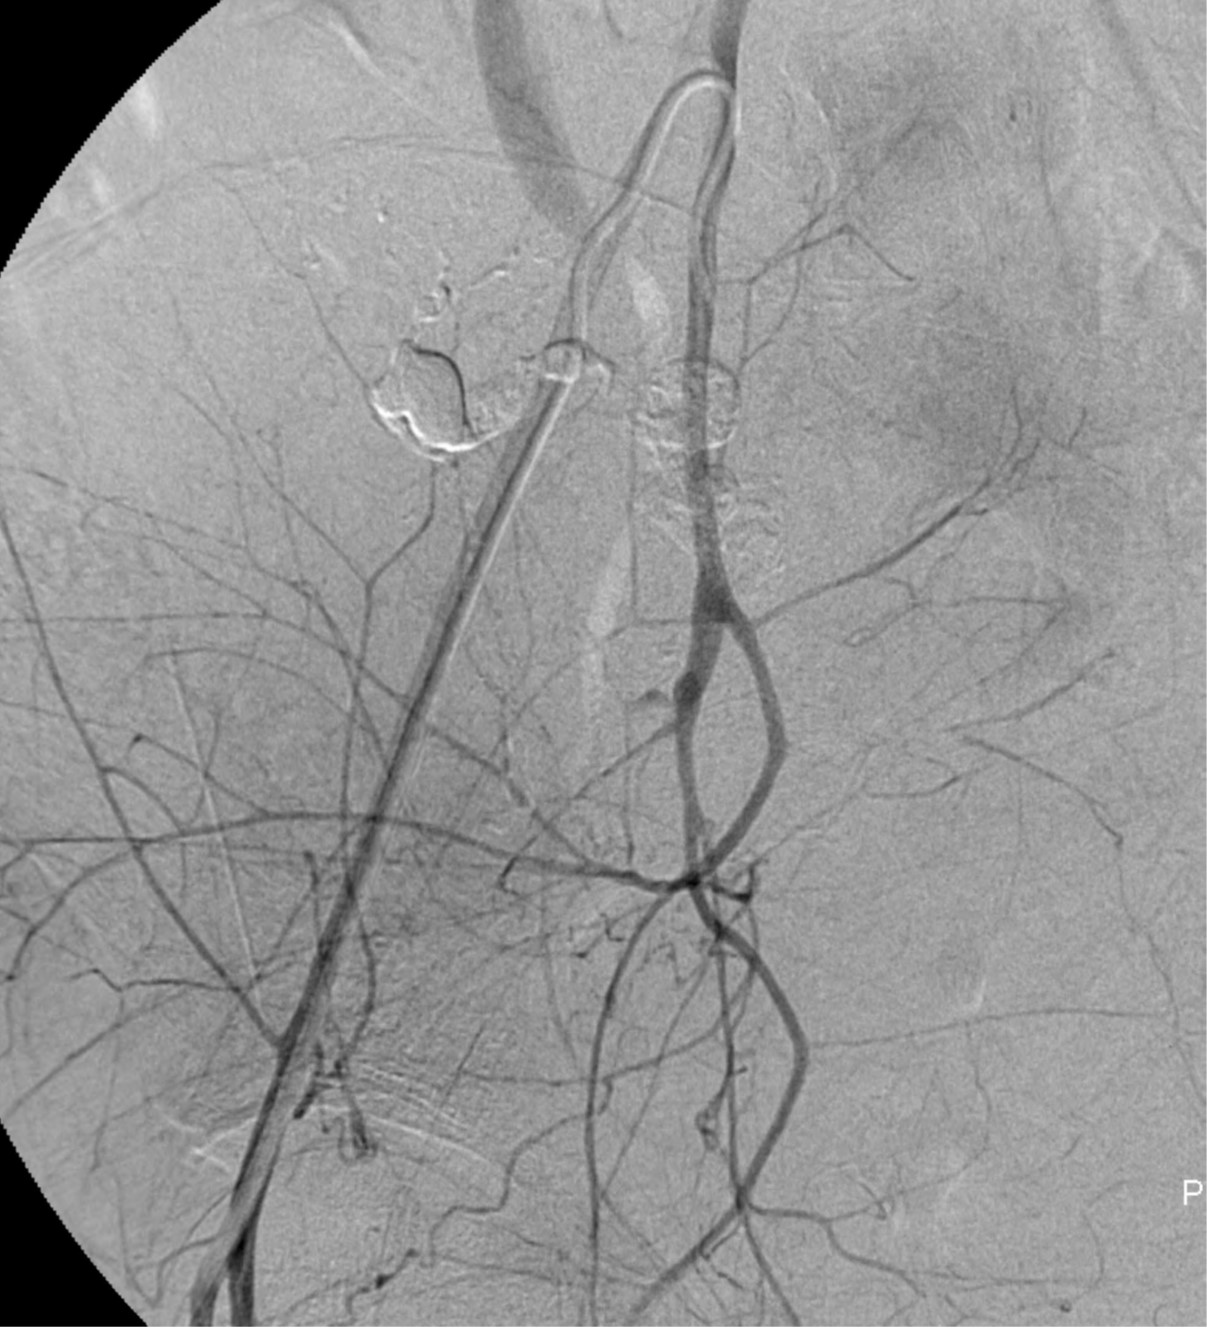

Fig. 1.

Right internal iliac angiogram with left anterior oblique projection shows very tortuous and dilated right uterine artery (arrows) and formation of pseudoaneurysm (arrowheads).